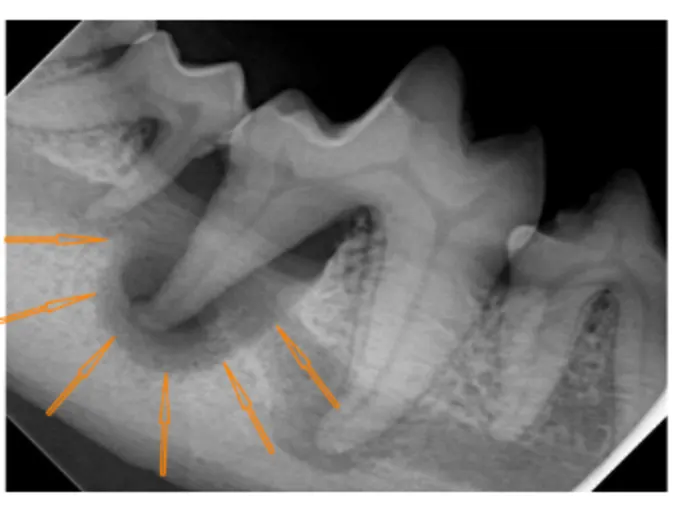

This x-ray shows a tooth root abscess results in bone loss around the entire root. The orange arrows outline the missing bone which has been replace by pus.

Severe tartar, pus along the gemlike and very red/inflamed gums.